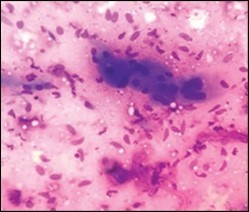

On gross examination, a tan coloured, gritty nodule, confined to the sternocleidomastoid muscle is delineated. Characteristically, smears obtained by fine needle aspiration cytology are composed of bland appearing, plump or normal fibroblasts and proliferating fibroblasts with an admixture of degenerative, atrophic skeletal muscle cells, giant myocytes with several nuclei, scattered, bare, bland nuclei or cells with fragmented, wispy cytoplasm and parallel aggregates of fibroblasts. The background is clear and devoid of cellular or nuclear debris. Sheets of spindle-shaped fibroblasts, atrophic muscle fibres and regenerating, multinucleated muscle giant cells are intermingled with the fibroblastic component 5, 6.

Figure 5.Fine needle aspiration cytology of fibromatosis colli exhibiting aggregates of spindle- shaped cells, plump fibroblasts, fibro-connective tissue fragments and a clear background with minimal red cell extravasation 12.

Fine needle aspiration  cytology of                     fibromatosis colli exhibiting aggregates of spindle- shaped cells, plump fibroblasts,                fibro-connective tissue fragments  and a   clear background with minimal red cell             extravasation 12.